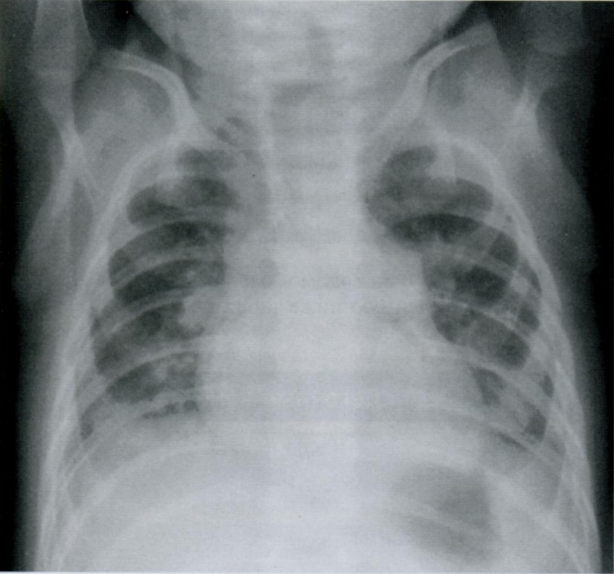

Ниже представлен снимок того же ребенка, который перестал плакать и лаборант успел выполнить повторный снимок.

Мы видим нормальную рентгенограмму грудной клетки (чистые легочные поля), и аэрофагию (18) - воздух в желудке, проглоченный во время плача.

Мораль: необходимо определить в какой фазе дыхания был выполнен снимок + ВСЕГДА иметь клинический контекст.